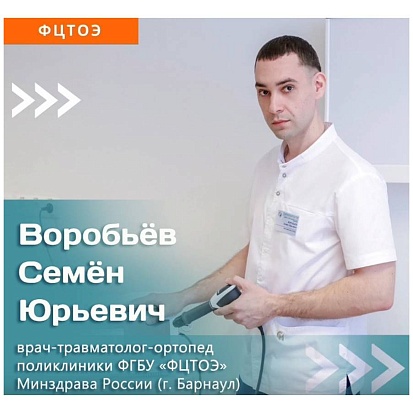

Ударно-волновая терапия

Ударно-волновая терапия